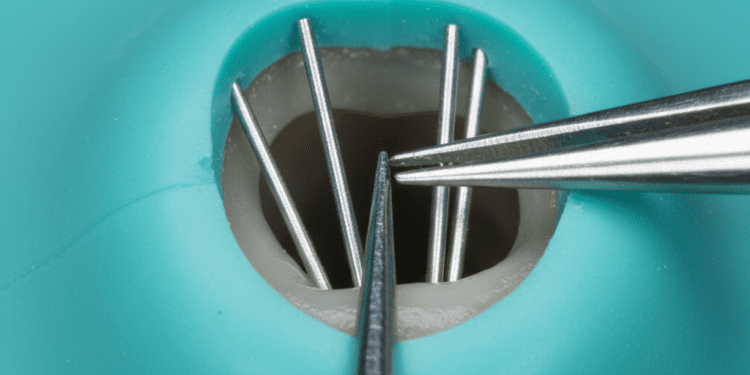

Quando a recessão alcança níveis significativos, procedimentos cirúrgicos podem ser necessários para restaurar a margem gengival. Entre as técnicas mais comuns, destacam-se:

- Enxerto gengival livre: Consiste na retirada de tecido gengival da região do palato para cobertura da raiz exposta.

- Enxerto de tecido conjuntivo: Técnica que utiliza uma camada do tecido abaixo da gengiva do palato para recobrir a área afetada, favorecendo a cicatrização e a formação de nova gengiva.

- Retalho gengival: Levantamento da gengiva local para reposicionamento e melhor cobertura da raiz.

- Uso de membranas ou substitutos gengivais: Em alguns casos, materiais biocompatíveis são aplicados para auxiliar na regeneração dos tecidos.